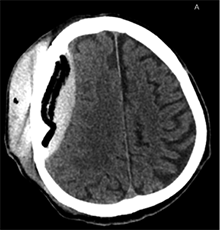

Po 2 savaičių pacientas rastas parkritęs kieme. Buvo matyti kraujuojanti žaizda. Pacientas pakartotinai hospitalizuotas į Neurochirurgijos skyrių. Atlikus GKT, nustatyta 25 mm storio hipodencinė juosta virš dešiniojo smegenų pusrutulio ir 8 mm vidurinių smegenų struktūrų dislokacija (VSD) į kairę (3 pav.). Įtariant lėtinę SDH dešinėje pusėje, pacientas reoperuotas, atliekant rekraniotomiją. Operacijos metu ant kietojo smegenų dangalo (KSD) rasta fibrino, jis pašalintas. Pravėrus KSD, rastas drumstas turinys, nesant aiškių pūlių, ir stora kapsulė. Gausiai praplauta šiltu fiziologiniu tirpalu subduraliai. Kaulinis lopas grąžintas (4 pav.). Po operacijos pacientas pradėjo skųstis stipriu galvos skausmu, tapo vangus. GKT pakartota. Įtarta empiema, nustatyti oro tarpai subduraliai, galvos smegenų VSD – 6 mm. Praėjus 12 dienų po antros operacijos, pacientas operuotas pakartotinai. Operacijos metu atlikta rekraniotomija. Epiduriniame ir subduriniame tarpuose rasta pūlių ir fibrino. Pūliai ir fibrinas pašalinti, paimtas bakteriologinis pasėlis. Žaizda gausiai praplauta šiltu fiziologiniu tirpalu. Kaulinis lopas negrąžintas, minkštieji audiniai susiūti (5 pav.). Po operacijos paciento būklė stabilizavosi. Bakteriologiniame pasėlyje negausiai užaugo E. coli, jautri ampicilinui. Nesant teigiamo efekto gydant ampicilinu, dar 2 savaites pacientui skirta gentamicino. Praėjus 3 savaitėms po trečios operacijos, pacientas perkeltas į slaugos ligoninę palaikomojo gydymo.

4 pav. Po antrosios operacijos (didžioji hematomos dalis pašalinta; VSD sumažėjo nuo 8 iki 5 mm)